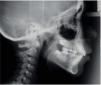

Radiographic analysis. A hyperdivergent skeletal class I was diagnosed (Figure 3). In the panoramic X-ray (Figure 4) the presence of the right deciduous second molar and inadequate root parallelism may be observed.